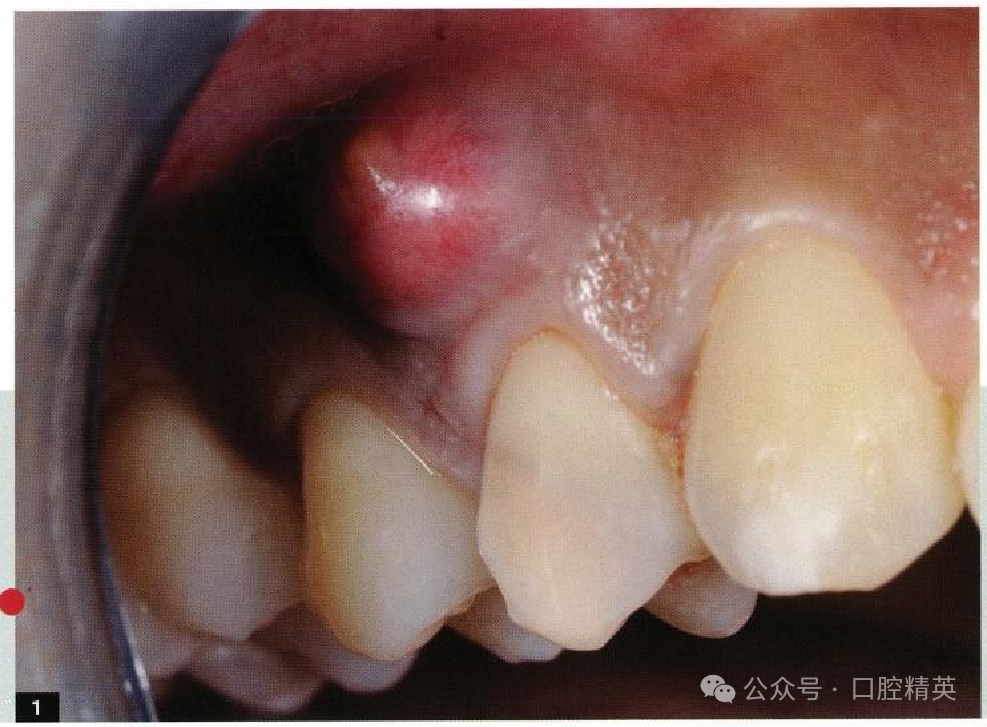

1、如何评估根管治疗成败的时机?

图:1疼痛肿胀是牙髓源性根尖周病变的典型临床症状之 一。